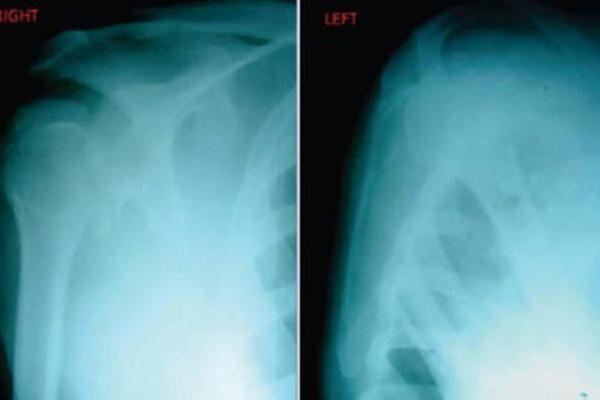

A 48 year old male presented to our emergency department with pain and restriction of movements involving both shoulders following a fall. The patient was standing by the side of a two wheeler when he had a sudden syncopal attack and toppled on the other side of the vehicle. On examination there was flattening of deltoid contour with a positive Dugas test in both sides. Humeral head was palpable posteriorly on the right side and anteriorly on the left side. Plain radiograph anteroposterior view of both shoulders showed posterior dislocation of right shoulder with a fracture of greater tuberosity and anterior dislocation of left shoulder with a greater tuberosity fracture. Closed reduction was achieved for both shoulders under general anaesthesia. After a couple of weeks, complete range of motion exercises was started. X-ray of bilateral shoulders, at 3 months, showed complete union of the fracture.